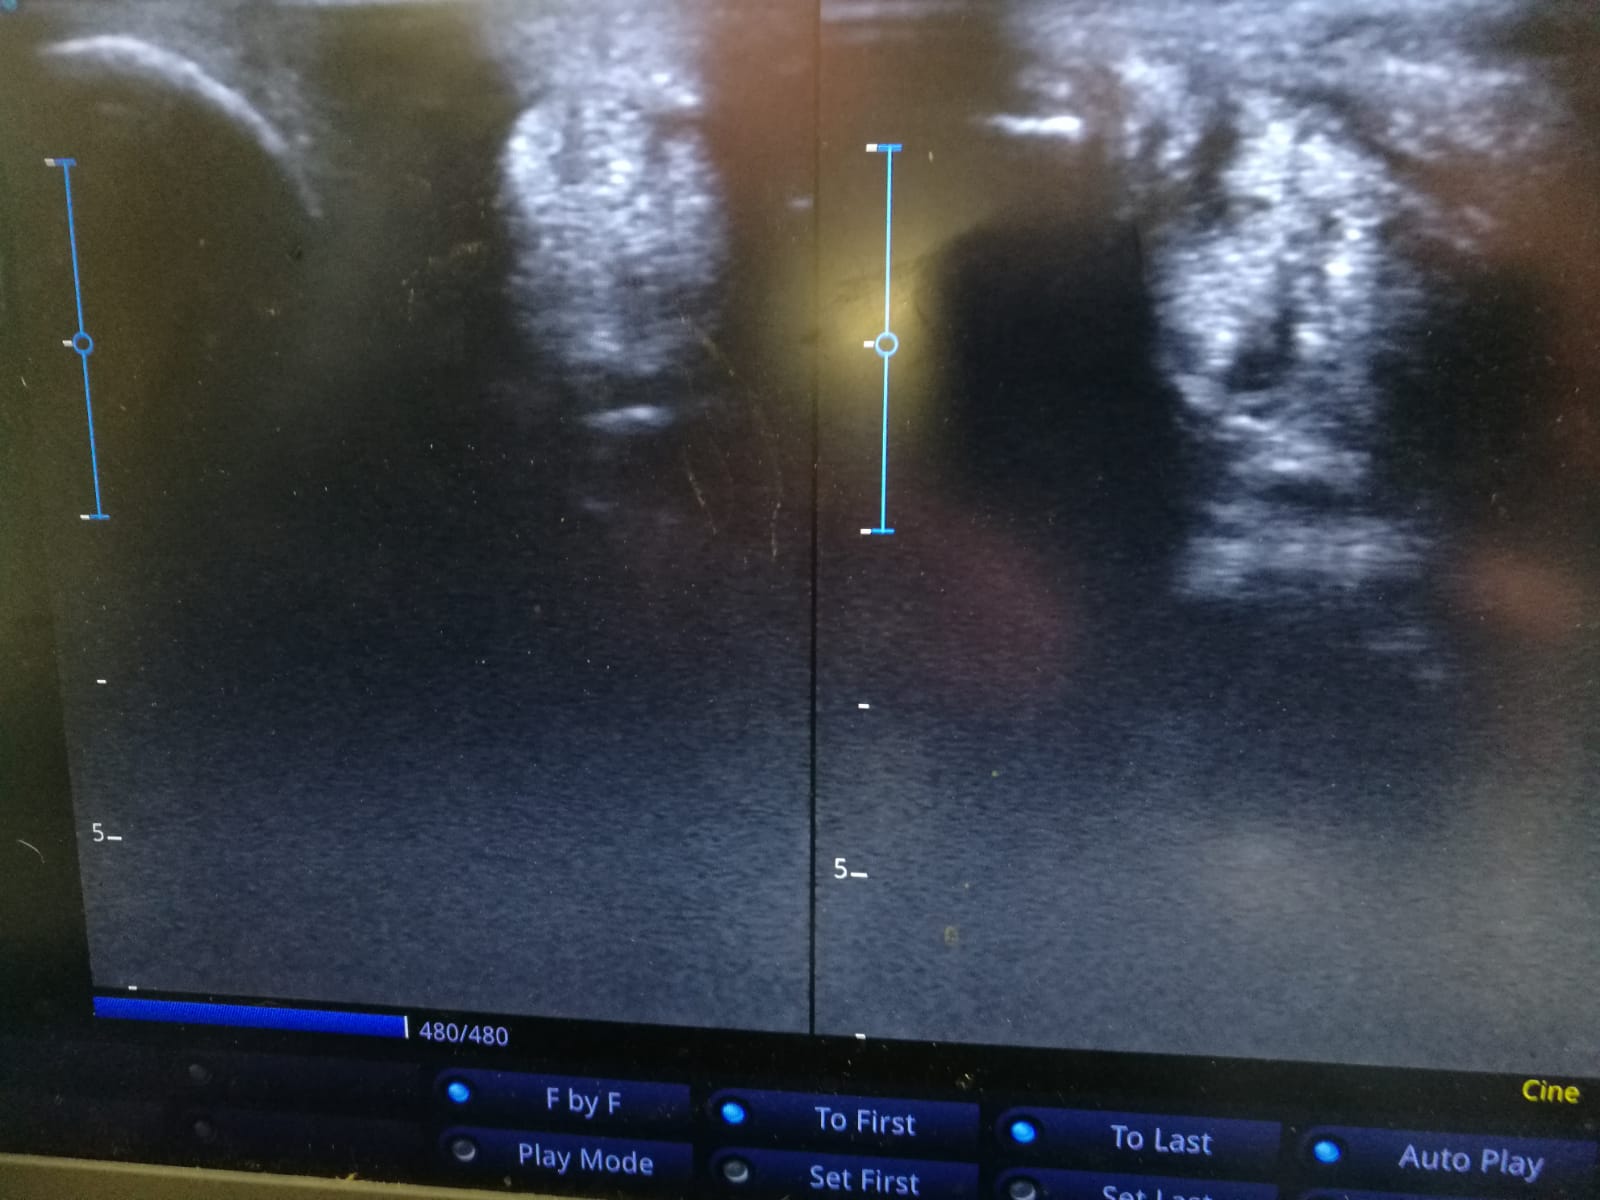

Добрый день дорогие участники форума, хочу обратиться за советами и комментариями. Неделю назад конь 14 лет споткнулся на ровном песочное плацу. После разминки 15 мин, на рыси. Перешли на шаг, не хормал, попросила пиафф- выдал что то непонятное, я попросила ещё раз- та же фигня. Сразу спешила, провела в руках- не хромал. Расседлала, выпустила в леваду- конь на заднюю правую не встаёт. Вызвали ветеринара- он смог приехать только вчера( прошла неделя) За эту неделю я отливала холодной водой, ставила димексид с диклофенаком. Два дня конь почти не ходил, ногу держал налегке. После двух трех дней начал ходить по леваде, не хромая. Я начала ходить с ним по асфальту по 5-8 минут, несколько раз в день. Вчера сделали узи, разорваны сухожилия ( если я правильно поняла - я не особо знаю терминологию на финском) Ветеринар посоветовал продолжать компрессы через день, холодные компрессы три раза в день, ходить продолжать по 10 мин несколько раз в день. Не бинтовать. Магнитные ногавки на ночь. Через два месяца проверка узи. Может кто умеет читать узи, насколько сильное повреждение? И может кто из собственного опыта подскажет ещё что нибудь.

IMG-20210803-WA0001.jpg

IMG-20210803-WA0000.jpg

Из моего опыта с лошадью с броком, дыра приличная, но не критичная.